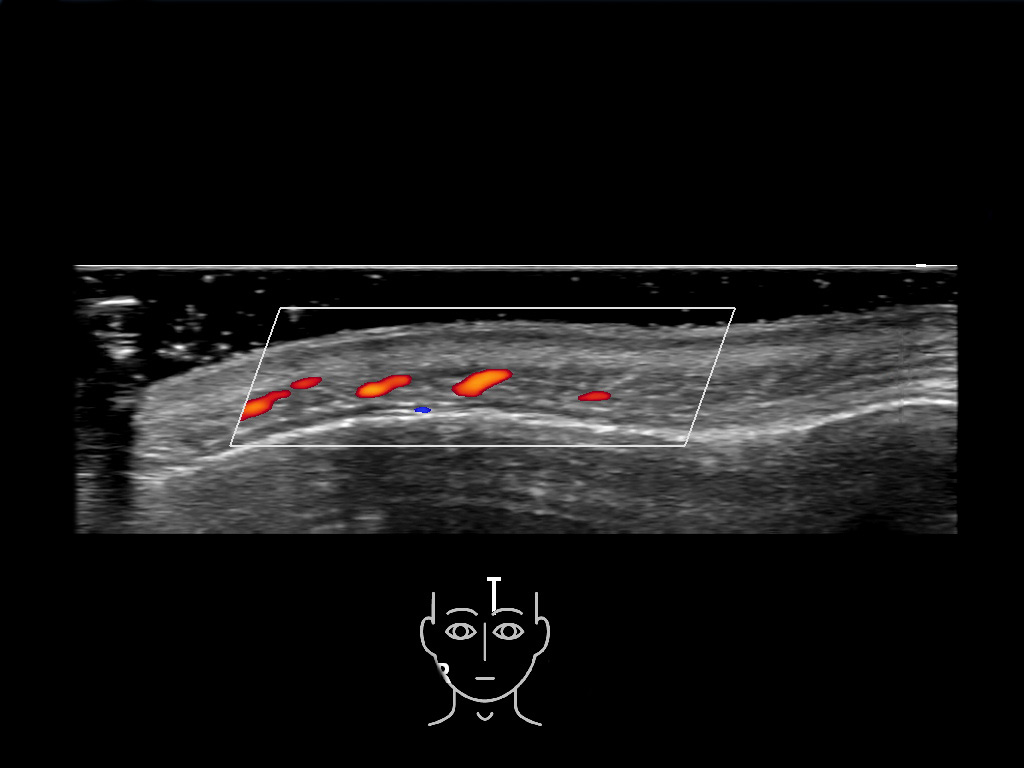

In this section you will learn more about the different layers of the face with the use of ultrasound. When you click on the secondary ultrasound image, you will see the different structures as an overlay. This will help to train yourself to recognize the different layers of the face.

Study the first image to recognize the different layers. If you are sure about the layers, swipe to the second image to view the answer (if applicable).